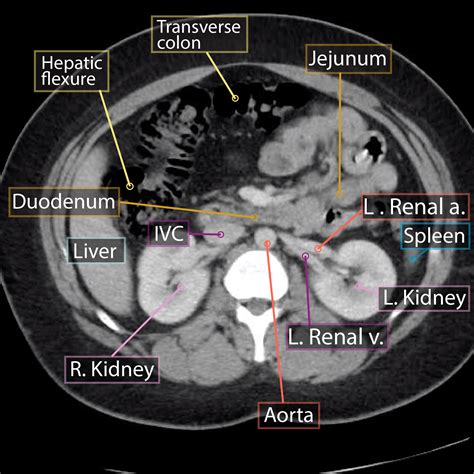

A Normal Abdominal CT scan, or Computed Tomography scan, is a non-invasive imaging procedure that uses X-rays and computer technology to create detailed images of the abdomen. These images help doctors visualize the internal structures, including the liver, spleen, pancreas, kidneys, and intestines. The term "normal" refers to the absence of any abnormalities or pathologies in the scanned area.

Common Findings in a Normal Abdominal CT Scan

When a Normal Abdominal CT scan is performed, several key findings are expected:

• Clear Organs: The liver, spleen, pancreas, and kidneys should appear clear and free of any masses or cysts.

• Intact Bowel: The intestines should be intact with no signs of inflammation, obstruction, or perforation.

• Normal Vascular Structures: Blood vessels should be clear and free of any blockages or aneurysms.

• No Fluid Accumulation: There should be no abnormal fluid accumulation in the abdominal cavity.

• abdominal ct scan anatomy